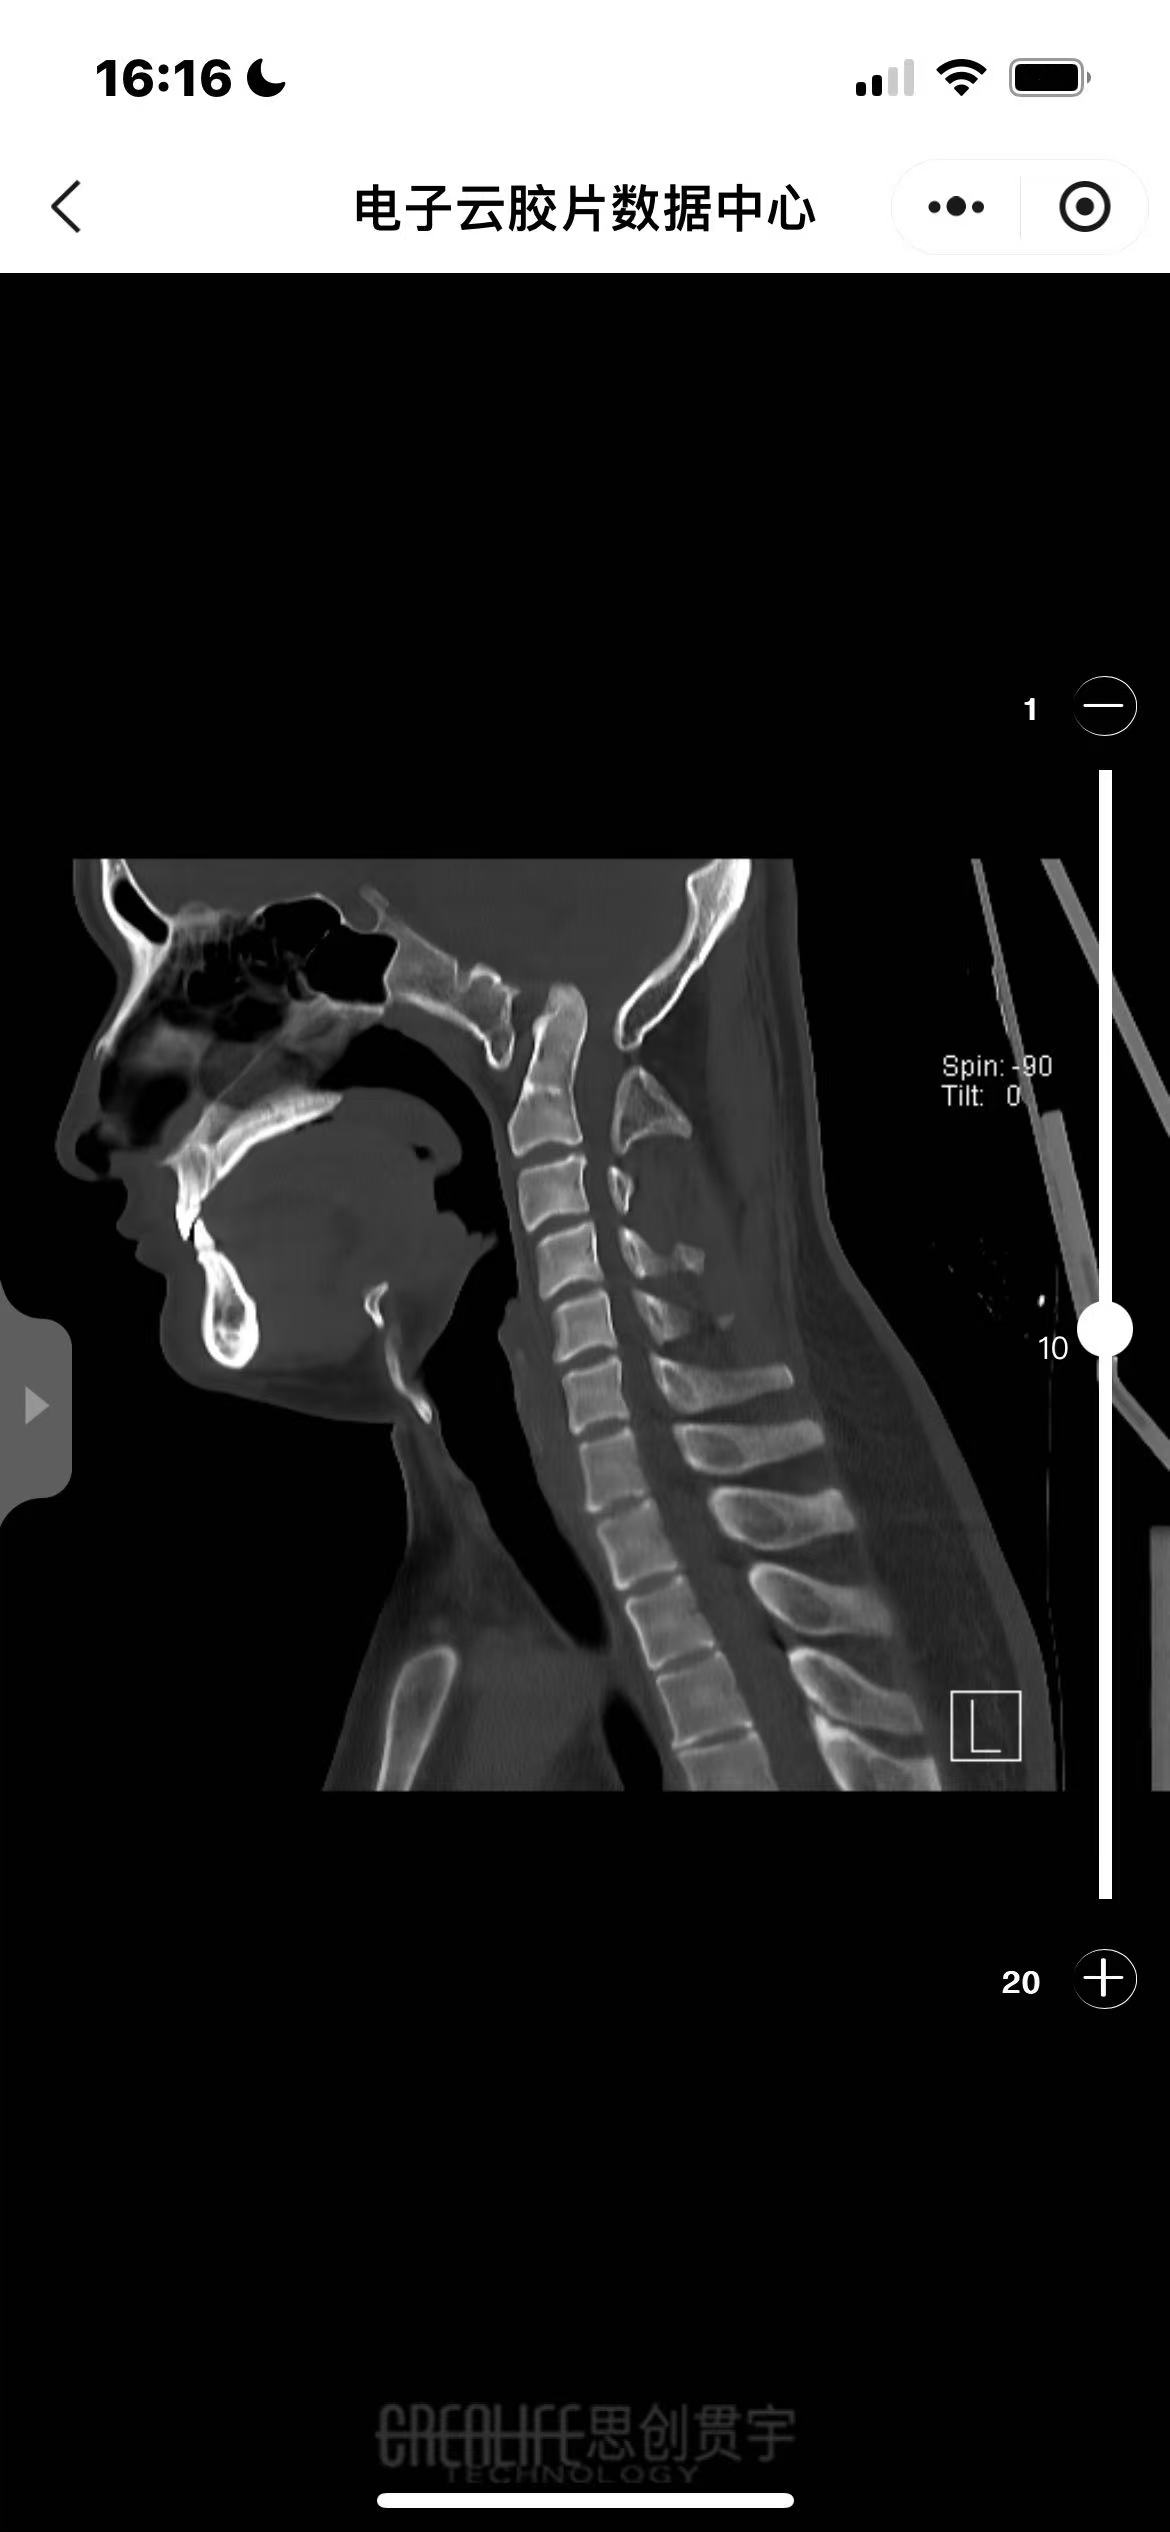

• 诊断:寰枢椎脱位、颅底凹陷

• 影像: